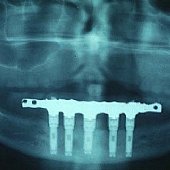

Bilder: Zahnimplantate bei Zahnlosigkeit im Unterkiefer

• Röntgendarstellung einer fest sitzenden Unterkieferbrücke mit 5 Implantaten.